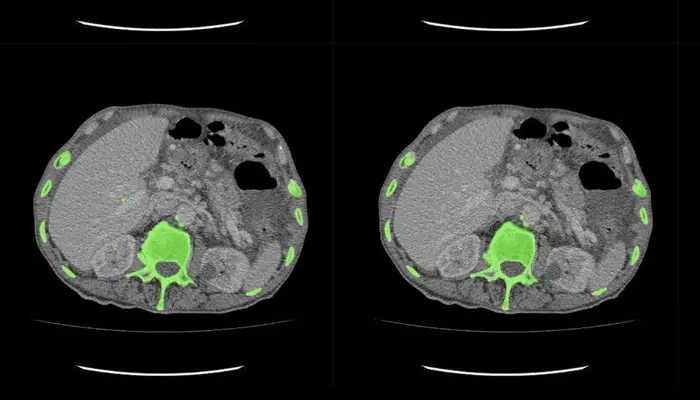

This process consists of finding areas of interest, marking areas of abnormality, segmenting certain organs/tissues, and labeling them to specific medical conditions.

Data labelling with AI can assist in building datasets of a high enough quality required to teach models to identify issues like fractures, tumors, lung disease, and abnormal organs in radiology scans, CTs, MRIs, and ultrasounds.

For the purposes of improving advanced 3D visualization, planning the beaming of radiotherapy, and surgical navigation, the segmented organs, tumors, and tissues must be accurately done.

The ability for precise medical labeling through the support of annotations for segmentation, bounding boxes, class, landmarks, and volumetric polygons.